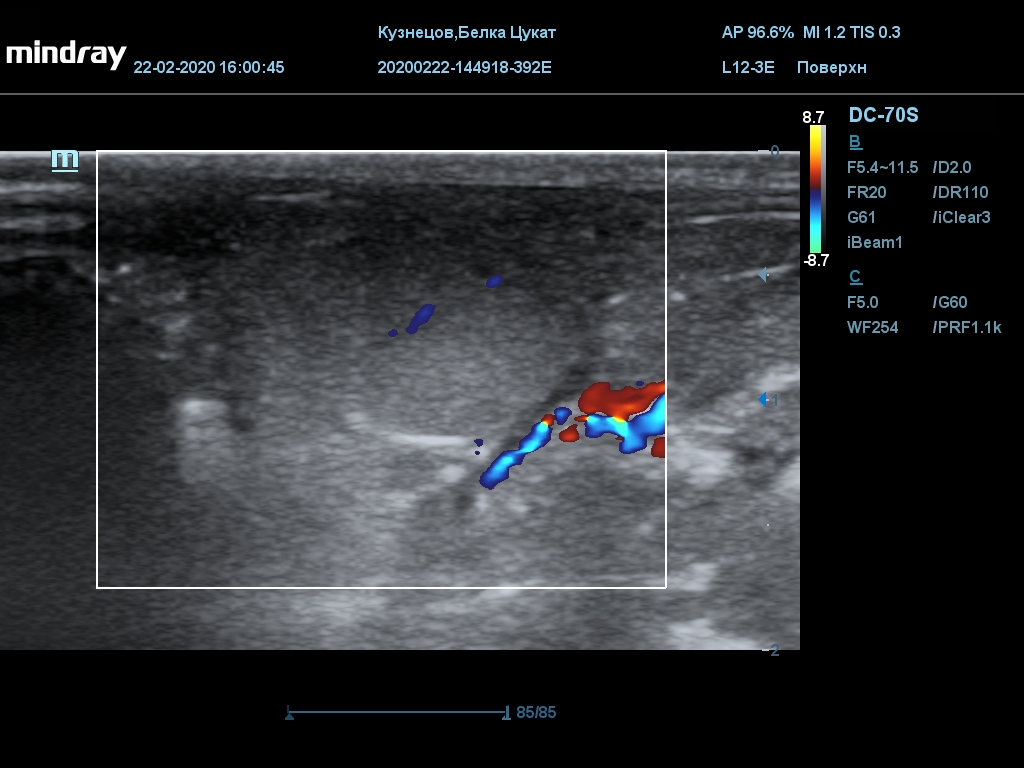

УЗИ

(почки, мочевой пузырь и, предположительно, простата)

Обращаю внимание, что делала УЗИ и писала заключение узист, которая специализируется на кошках и собаках, поэтому она сделала узи и описала, как смогла, но тонкостей грызунячьей анатомии она не знает.

Приложил только фото, есть ещё пара видео, но не знаю, как тут выложить, и надо ли.

Каудальнее мочевого пузыря визуализируется округлая структура размером 11,1 х 8,3 мм с ровными контурами гипоэхогенная однородная, с признаками васкуляризации.

Заключение: УЗпризнаки уролитиаза, объёмная структура каудальнее мочевого пузыря. Признаки расширения левой лоханки.

УЗИ

(почки, мочевой пузырь и, предположительно, простата)

Обращаю внимание, что делала УЗИ и писала заключение узист, которая специализируется на кошках и собаках, поэтому она сделала узи и описала, как смогла, но тонкостей грызунячьей анатомии она не знает.

Каудальнее мочевого пузыря визуализируется округлая структура размером 11,1 х 8,3 мм с ровными контурами гипоэхогенная однородная, с признаками васкуляризации.

Заключение: УЗпризнаки уролитиаза, объёмная структура каудальнее мочевого пузыря. Признаки расширения левой лоханки.